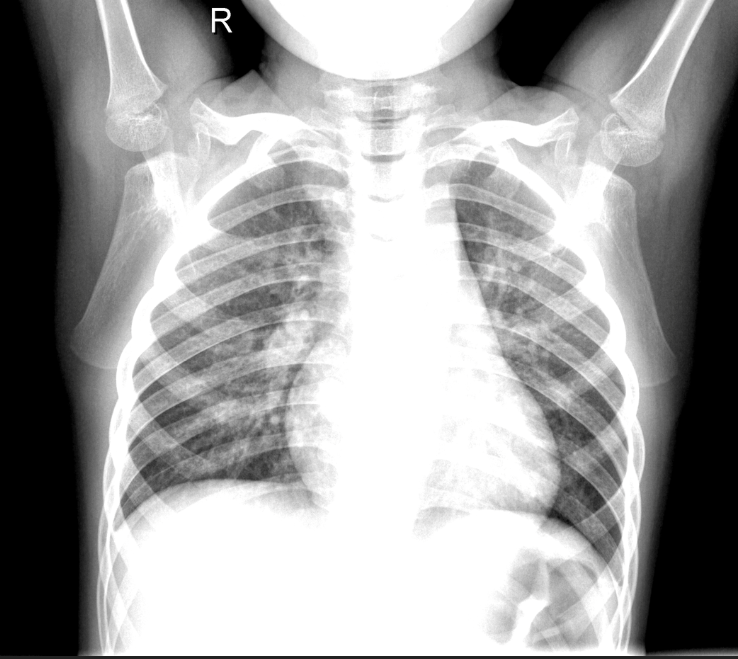

Another drawback for the early diagnosis of pneumonia is the human-dependent detection. Expert radiologists need to have sufficiently trained eyes in order to be able to differentiate between the heterogeneous color distribution of air while flowing in the lungs. This may be seen in different colors on the x-ray image taken, yet not be the dense pneumonia fluid. Thus, it’s highly significant for a radiologist to be able to tell whether if the white spots on the x-ray film actually correspond to the fluid itself. As a result of the error margin of the human eye, there are many cases where the radiologists fail to make the correct diagnosis. In both cases, whether if it’s a false positive or false negative diagnosis, it has substantial impacts on the human body. Therefore, computational methods in the diagnosis step of the disease are reliable in terms of consistency. In fig 1, different images with and without pneumonia can be seen ([2]). The imperceptibility of the healthy versus the pneumonia images can also be witnessed, which portrays the need of well-trained eyes in order to be able to differentiate.

Refer to caption

Figure 1: X-ray Images with and without Pneumonia